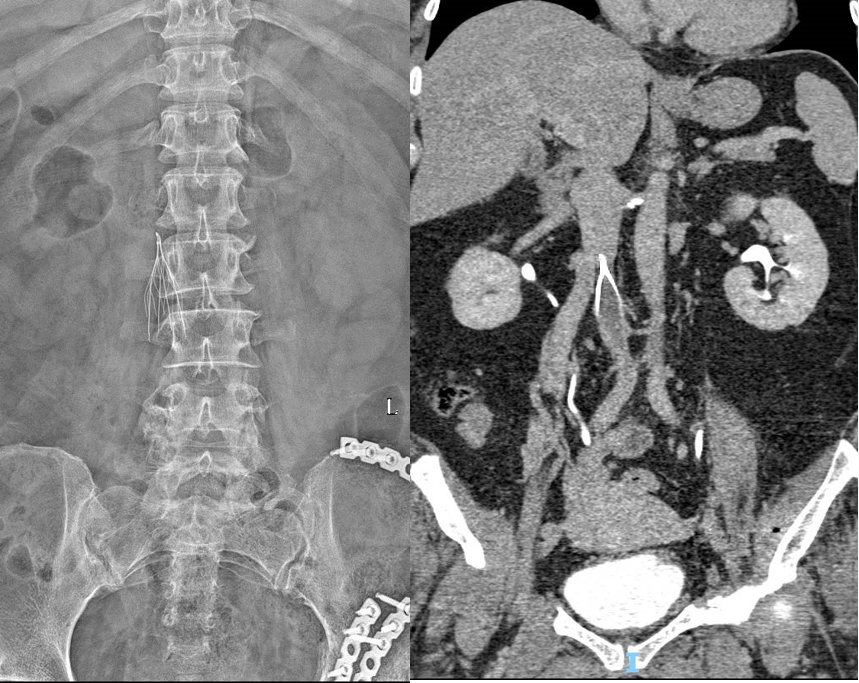

★ Case1:梭形滤器下腔静脉亚急性血栓

图:基线造影情况:右侧股静脉、双髂静脉、下腔静脉血栓性闭塞

★ Case3:锥型滤器慢性腔髂静脉血栓闭塞

23M,下肢骨折合并DVT,外院放置锥形腔静脉滤器3个月,发生慢性腔髂静脉阻塞;

双下肢运动后肿胀,伴沉重感;

未规范化抗凝治疗。